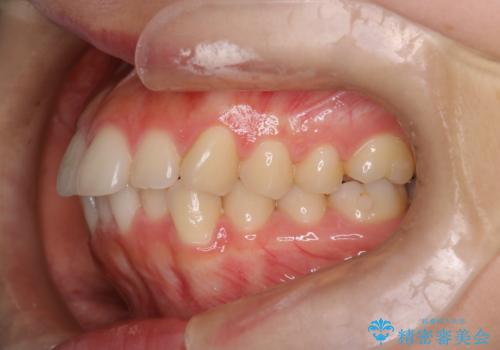

【インビザライン】前歯を下げたい

- 前歯が出ていることを主訴に来院されました。

奥歯を後ろに動かしながらスペースを作ることで、前歯を下げることができ患者さんにも満足していただきました。

治療中に顎間ゴムを使用していただいたおかげで、スムーズに治療を行うことができました。